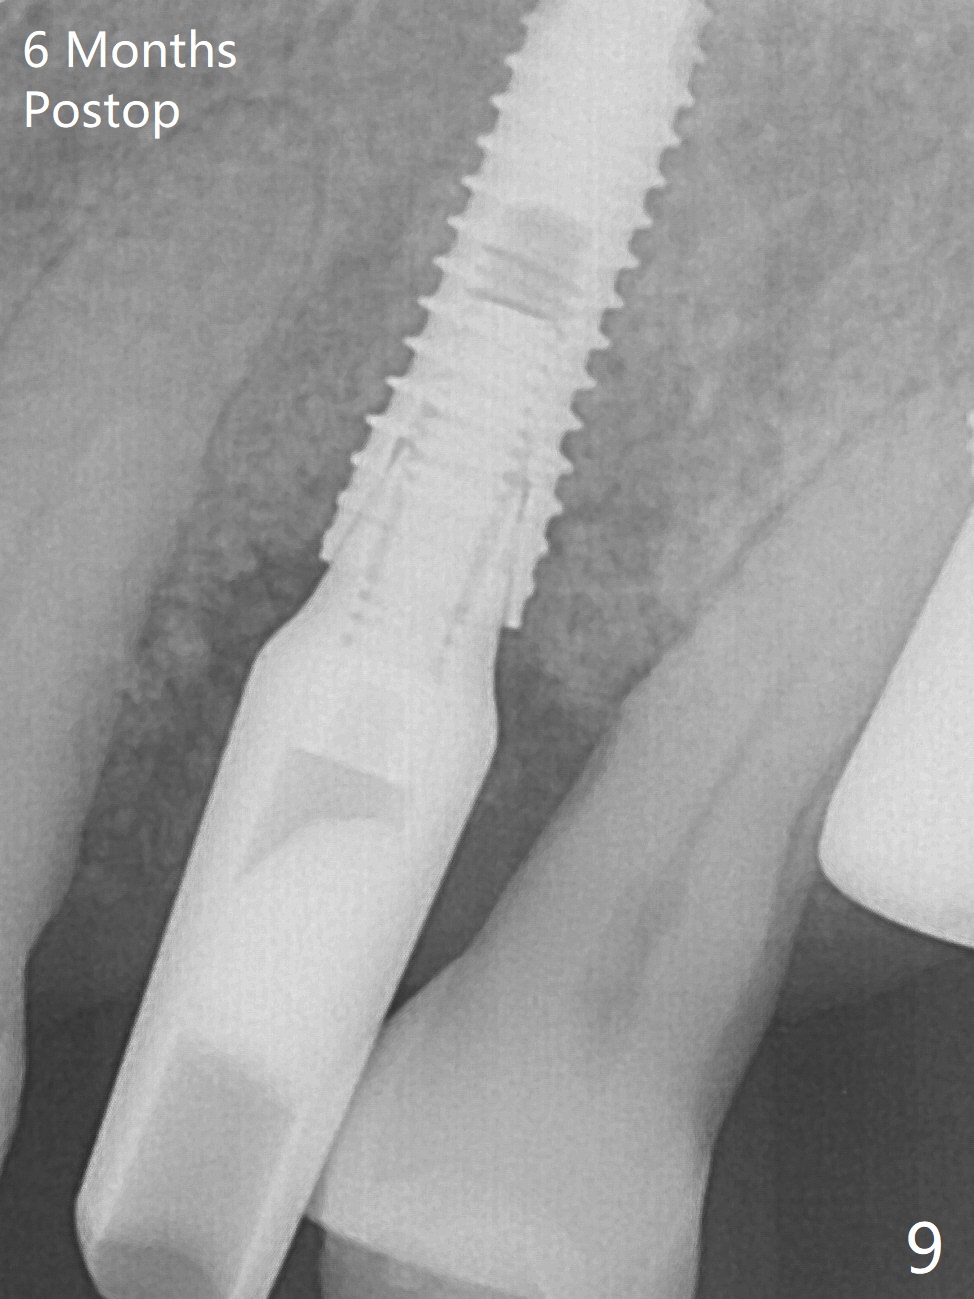

A few days prior to surgery, the tooth #12 developed abscess, self controlled by water pik (Fig.1 *). The buccal plate is defective. Initial osteotomy is close to the root of the tooth #11 (Fig.2). After adjustment of the trajectory and the depth of osteotomy (Fig.3), a 3.8x15 mm dummy implant is placed (Fig.4,5). In spite of a shorter implant (3.8x13 mm) placed deeper, approximately 7 mm implant threads are not covered buccally by the native bone (Fig.6 red dashed line). If the implant were placed deeper, the crown/implant ratio would become more unfavorable (abutment screw loosening, Fig.7). Since a mill abutment (4.5(2) mm) is inserted before Vanilla Graft, the deepest portion of the socket is unfilled (Fig.7 *). With meticulous use of a long explorer and additional allograft, the space is closed (Fig.8 *). The buccal plate collapses with apparently fistula formation 2 months postop. The patient removes the provisional for cleaning. It appears that the mill abutment is buccally placed and needs heavy reduction. The mill abutment is loose 2 months 10 days postop. When it is retightened, it tilts distal. Bone remains around the implant 6 months postop (Fig.9). Without a provisional at #12 for 5 months, the tooth #13 appears to have been shifted mesially (Fig.10 arrow). The mill abutment at #12 changes to a healing one. A lingual button is placed in the mesial surface of #13. Splinted provisional is fabricated with supraocclusion at #14 and 15 as an anchor (implants). The tooth #13 is being distalized with power chains. Limited ortho is finished nearly 2 months post banding (Fig.15,16).